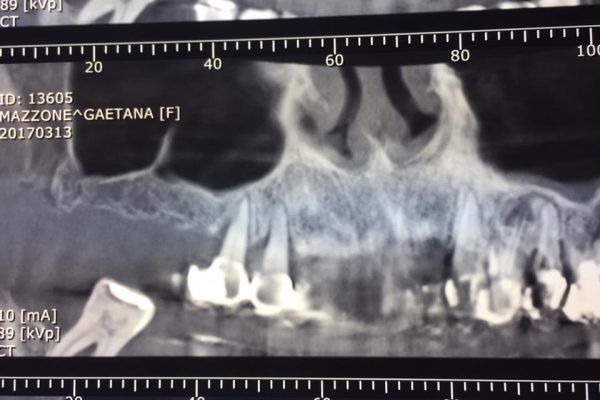

Inserimento impiantare in zona mascellare superiore di destra con insufficienza ossea verticale.

Esecuzione di rialzi di seno mascellare con tecnica transcrestale minimante invasiva …